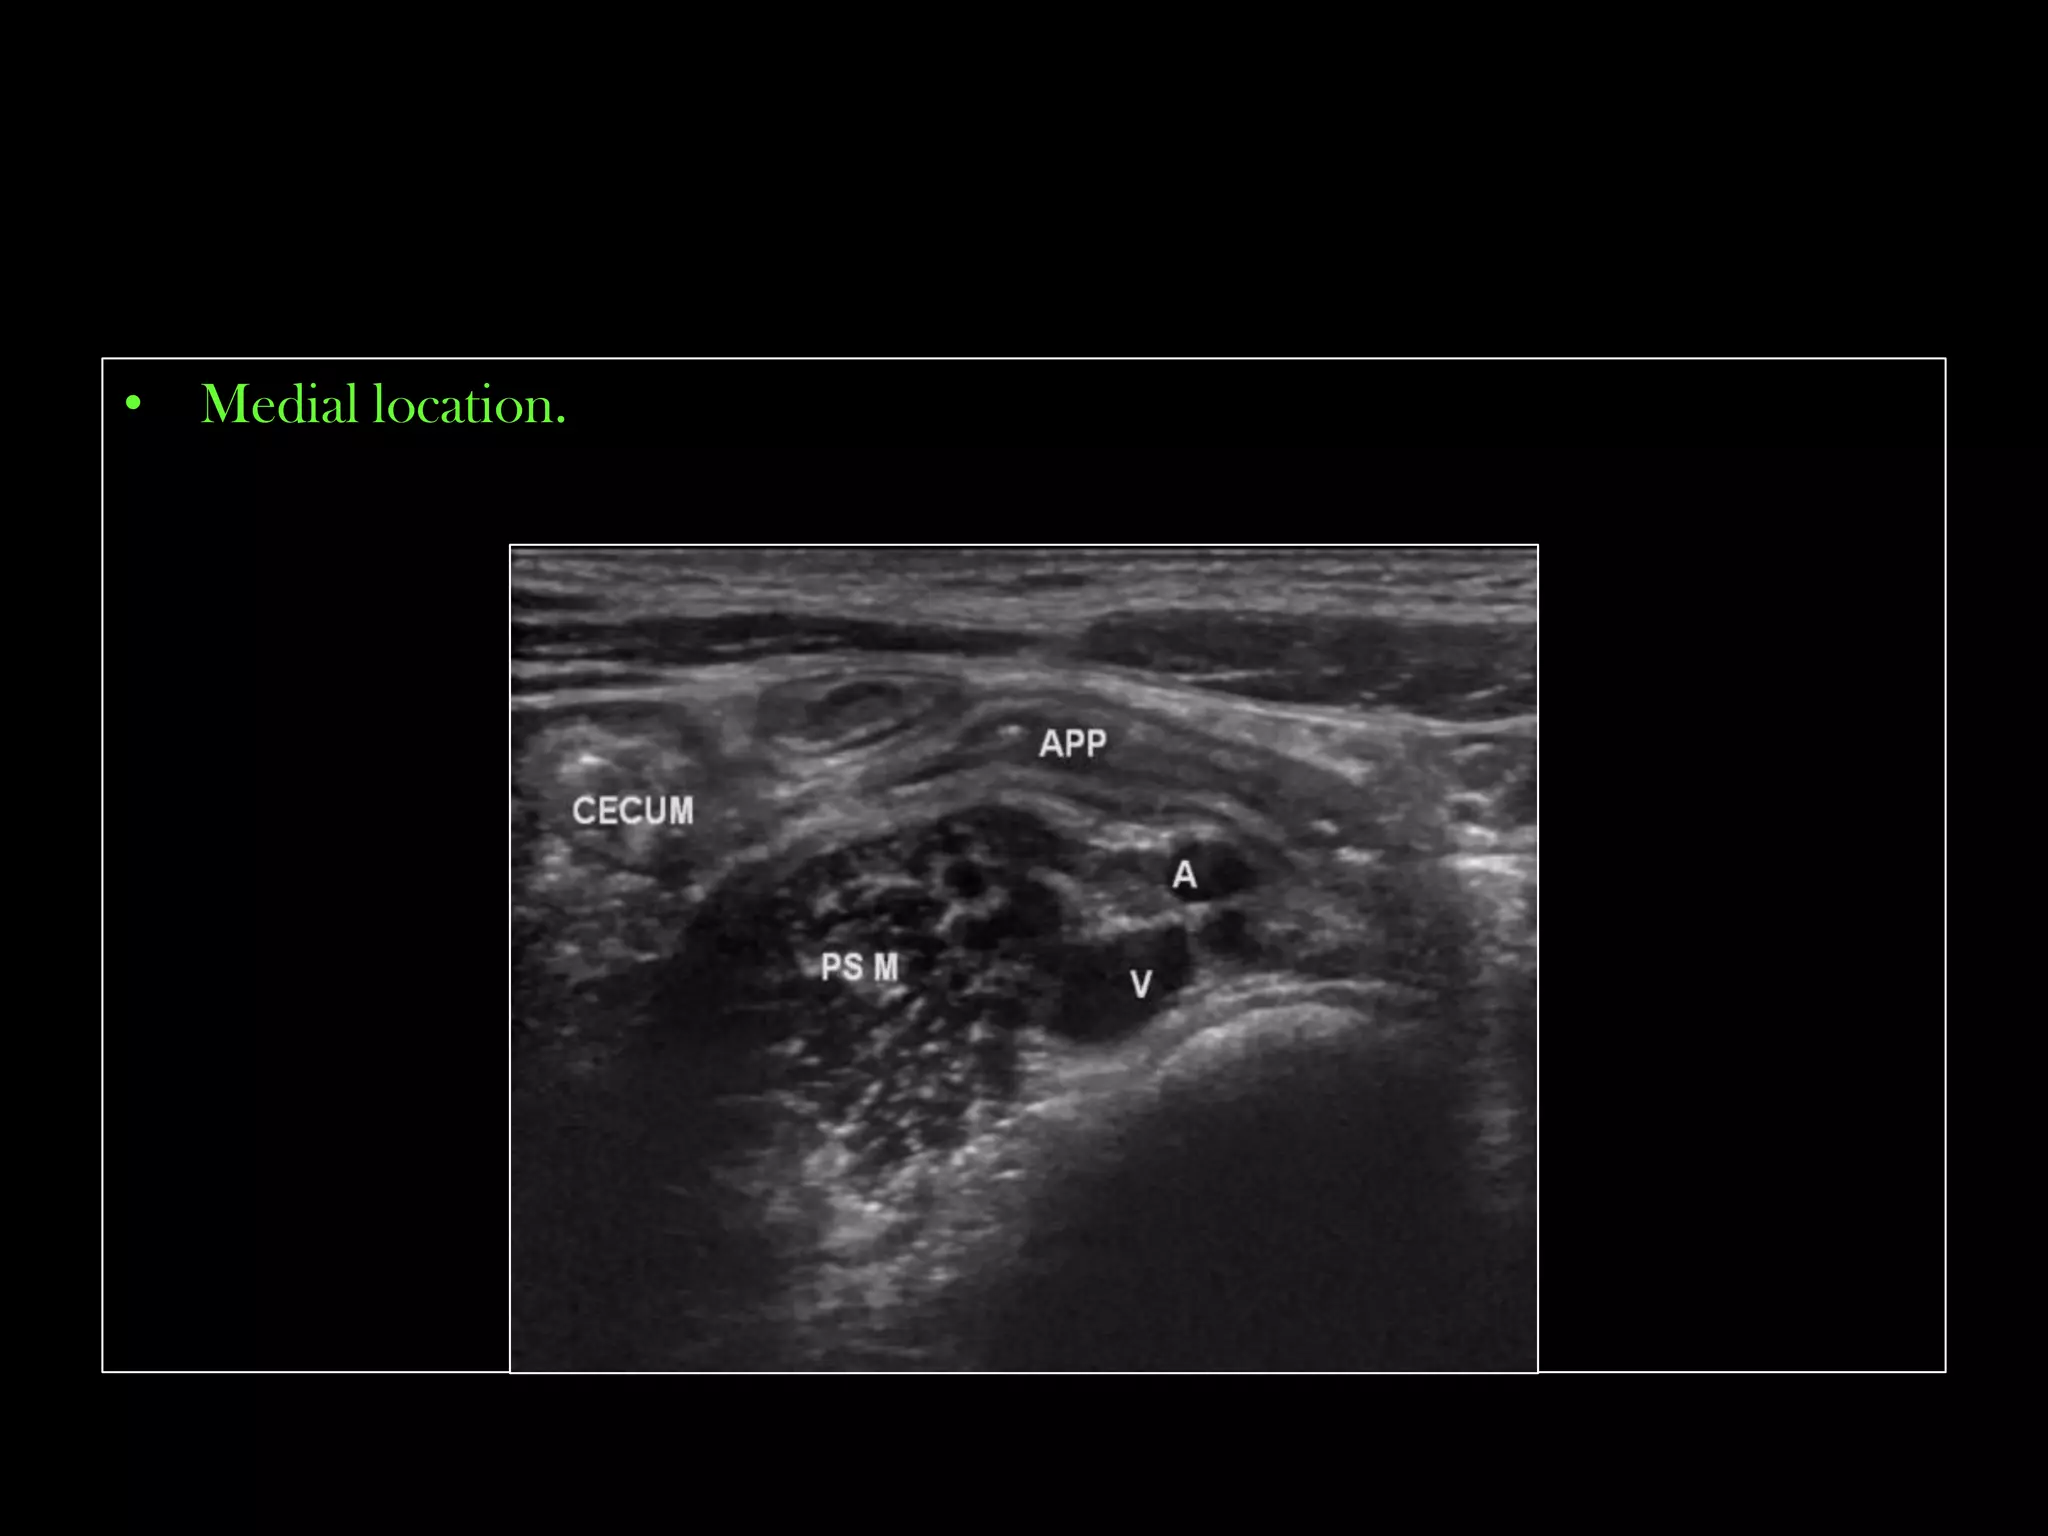

Appendix ultrasound — Kwak Talk